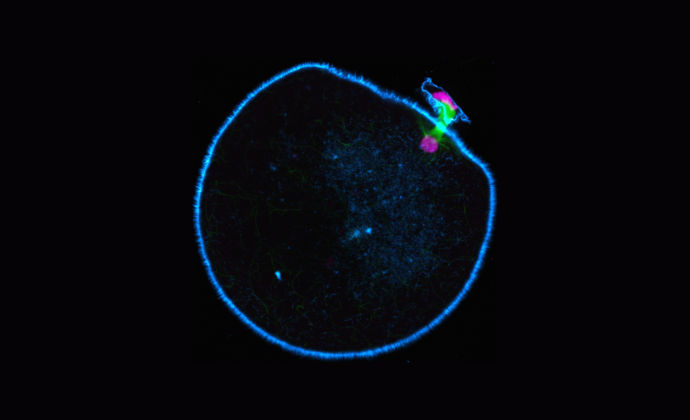

Molecular motors are biological machines responsible for movement inside the cell. During its formation, the immature egg, or oocyte, divides so that only half the maternal genetic material remains in the mature egg. To enable this to happen a spindle structure is formed that pulls the chromosomes apart. If the egg gets this wrong the resulting embryo will have too many or too few maternal chromosomes, a condition known as aneuploidy.

Research by Dr Melina Schuh’s group, has revealed remarkable differences in spindle organization in different mammals. Humans were found to be deficient in the molecular motor KIFC1 (kinesin superfamily protein C1), a key spindle-stabilizing factor found in the oocytes of other mammalian species.

Human oocytes are deficient in the molecular motor KIFC1 (kinesin superfamily protein C1), a key spindle-stabilizing factor in oocytes of other mammalian species.

Spindle stabilization is likely achieved via the formation of static crosslinks along parallel microtubules at the poles and the alignment of antiparallel microtubules in the central region of the spindle. Because human oocytes are deficient in KIFC1, the researchers propose that the deficiency of these activities renders their spindles unstable.